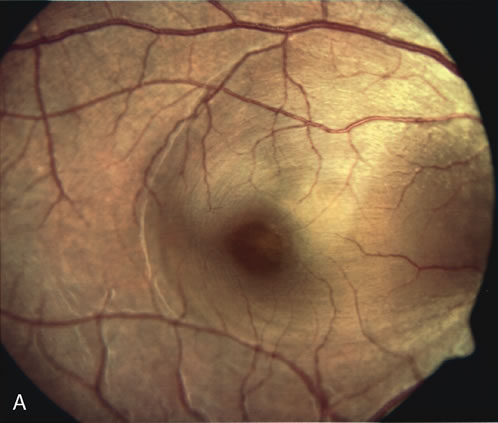

The diagnosis of degenerative myopic maculopathy is clinically obvious. Patients with pathologic myopia are, however, at risk for development of CNV, and FA is helpful in their diagnosis and treatment.251–255 Patients with myopic degeneration have pigmentary changes that can be difficult to distinguish from small neovascular membranes. CNV in pathologic myopia tend to be smaller and less aggressive than the neovascular lesions of age-related macular degeneration.55 CNV in myopic eyes can often be strongly suspected on clinical grounds, using clues such as subretinal blood or lipid exudate, neurosensory elevation, and appearance of a gray membrane visible through atrophic RPE (Fig. 38). FA is sometimes helpful in distinguishing a neurosensory detachment due to a small macular hole from retinal elevation from leaking CNV. FA has been also valuable in demonstrating an association between Fuchs' spots and CNVs254 and in identifying disturbances of choroidal and retinal blood flow in pathologically myopic eyes.255

Fig. 38. Myopic maculopathy with choroidal neovascular membrane. This patient's myopic degeneration is manifested by a large conus around the optic disc and prominence of the choroidal vasculature seen clearly through thinned retinal pigment epithelium. There is a large choroidal neovascularization (CNV) in the papillomacular area. Although CNV formation is common in myopic maculopathy, this lesion is unusually large.